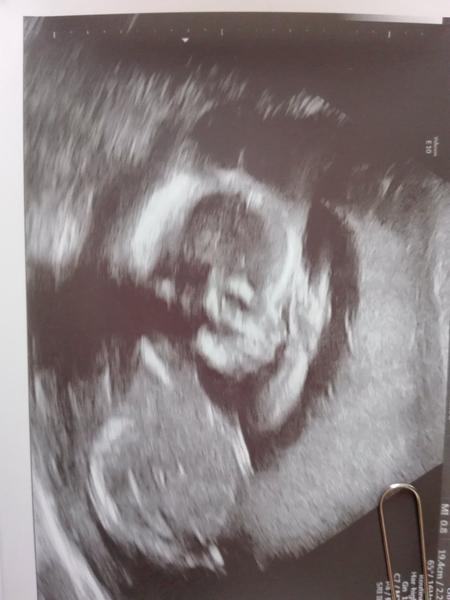

Tohle je prave fotka s 3D, ale na 3D to nebylo vidět, tak je to dělané z 2D. Miminko nechtělo vubec spolupracovat, tak ho sestřička ultrazvukem dost trápila a pak mi ukázala tohle. 😄

A nebo je fajn 3D utz,tam bylo zrno videt krasne 🙂